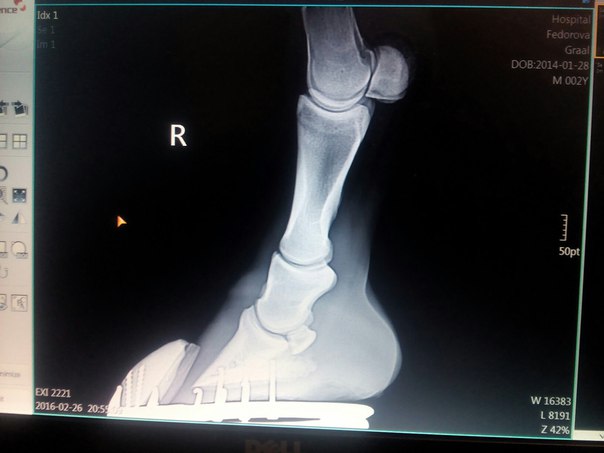

и буквально 2 нед.назад заметила что с передними ногами начинается беда, особенно с левой передней, начинается контрактура , бабка выходит вперед, созвонилась с ветеринаром, по ее рекомендациям ватники бинты в денник и гулять, до ее приезда, снять с овса. Пока ее ждали почти неделю, ноги стали хуже на левой ноге пятка выше стала . Вчера она до нас доехала , сказала, что есть шанс что то исправить , и такая проблема у него из-за его роста ,связки и сухожилия не успевают за ростом костей.